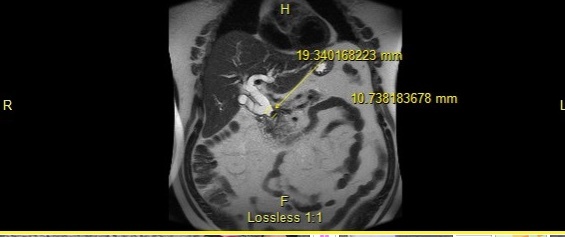

His laboratory values were significant for elevated total and direct bilirubin (22.4 and 15.9 mg/dl). Additional lab values include – an AST (137 U/L) and ALT (232 U/L), and an abnormally elevated Lipid panel with LDL (263 mg/dl), triglyceride (357 mg/dl), and total cholesterol (346 mg/dl). On day three of admission, the patient underwent an endoscopic retrograde cholangiopancreatography (ERCP) with findings significant for multiple gallstones in the common bile duct (Fig. 1 - 4) consistent with Mirizzi syndrome.

On the ERCP, patient had outpouching in the cystic duct. A stent was placed in the common bile duct (CBD). The patient’s direct bilirubin decreased from 7.4 mg/dl to 5.9 mg/dl. The patient was scheduled to follow up with gastroenterologist in two to three weeks for the removal of the CBD stent, and he improved markedly post-stent placement. He was asymptomatic on discharge.

Mirizzi syndrome is obstruction of the common hepatic duct from a stone impacted on the gallbladder infundibulum or cystic duct remnant. It has been classified into five variants (Table 1) based on the Csendes 2007 classification.1 It usually presents with right upper quadrant pain, with or without jaundice and fever.2 The most commonly used studies for diagnosing Mirizzi syndrome are the ultrasound, computed tomography (CT), magnetic resonance cholangiopancreatography (MRCP) but the endoscopic retrograde cholangiopancreatography (ERCP) is the most sensitive.3 It is reported to have a 100% sensitivity,3 and as seen in this case can be diagnostic for Mirizzi syndrome.